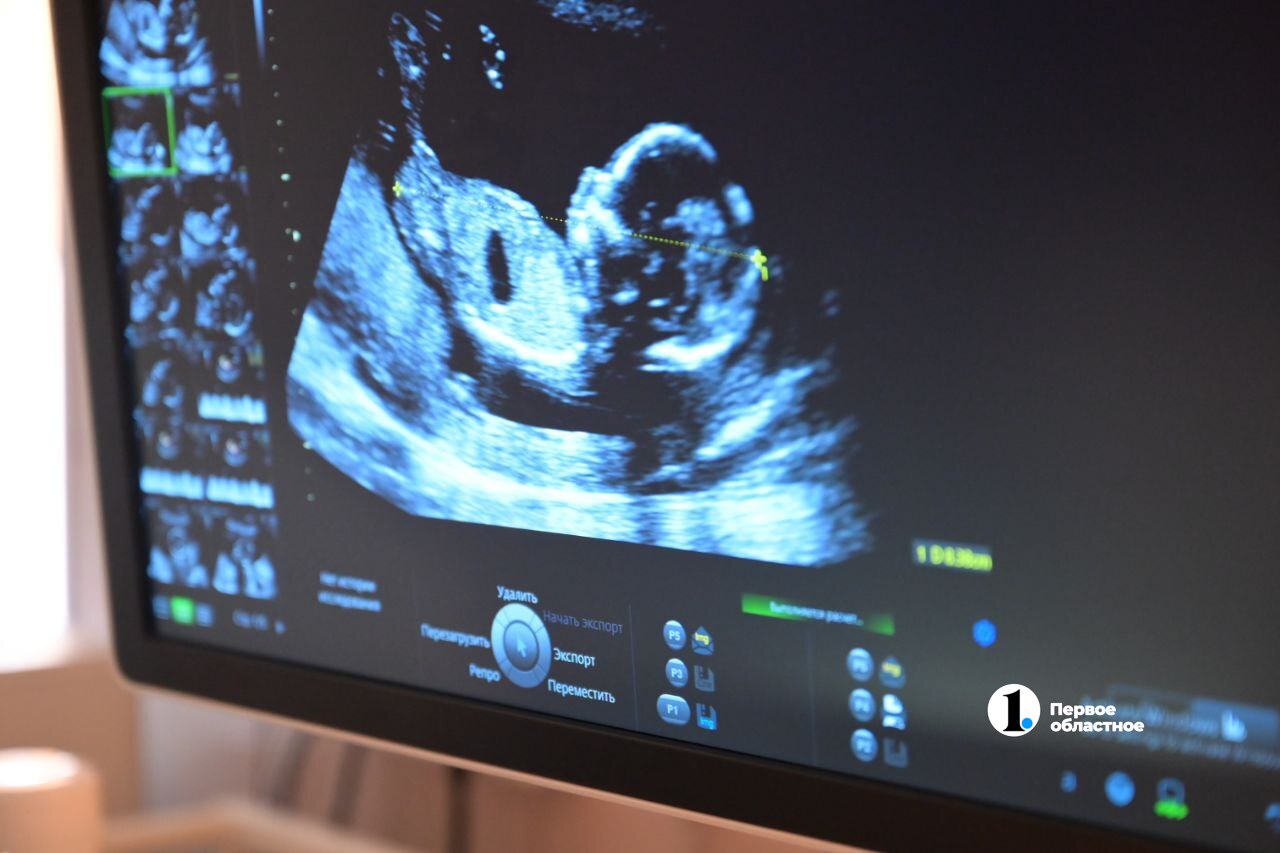

Свою профессию доктор считает самой необычной и захватывающей дух, ведь именно врач УЗИ видит, как зарождается новая жизнь, что похоже на чудо.

«Но вероятность порока не превышает и двух процентов. Большинству женщин мы приносим приятные и чудесные вести. Они сразу успокаиваются. А когда видят своего малыша на экране, то часто плачут от счастья», — рассказывает Мария.

Разглядеть пороки развития очень важно. Ведь многие из них можно исправить сразу после рождения, а то и в утробе и спасти жизнь крохе.

«Прежде всего, развиваются и растут. Некоторые детки очень спокойные — во время УЗИ они спят. Другие шевелятся, они активные. Благодаря современным технологиям мы можем увидеть, как они улыбаются, сосут пальцы, ловят ручками свои ножки, облизывают плаценту, играют с пуповиной, крутятся, вертятся, плавают. То есть делают абсолютно весь спектр движений, которые может совершать человек. Хотя удивительно: после рождения они лежат и даже не могут самостоятельно повернуться», — рассказывает Мария Токарева.